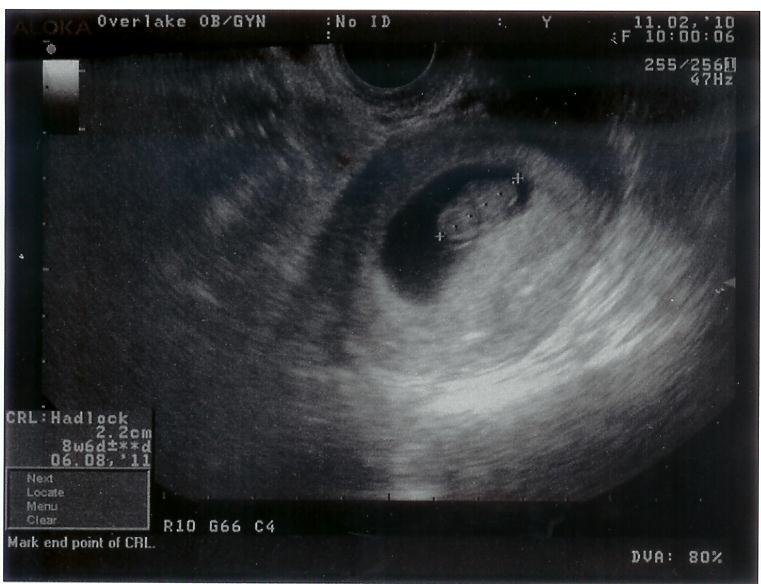

Our first ultrasound on November 2nd, 2010. The little peanut is less than an inch tall!

Our first ultrasound picture was an exiciting event. We finally got to see this little thing flutter around. It made the whole experience all the more real to us. Because Olivia was sick all the time, the doctor said, "it must be a girl". We are planning to wait till June to find out, so it will be a surprise for everyone!